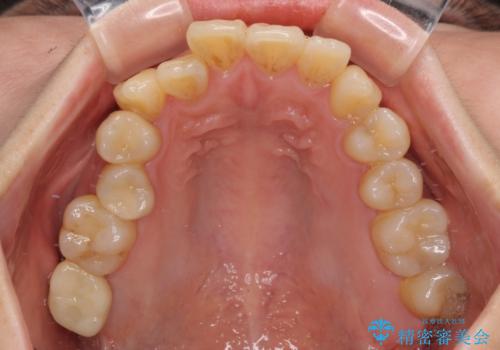

- 長年放置しているむし歯を気にして来院された患者様です。

外側を向いている上顎の奥歯は歯ブラシが十分に届かないため、むし歯となるケースが多いのですが、今回むし歯となってしまった歯がそれで、ボロボロになって根だけが残っている状態でした。

患者様と相談し、抜歯をした上でインプラントによる補綴治療を行うこととしました。

抜歯後に不快感は消失したのですが、手前の歯にあるむし歯が痛み出してきたため、セラミックインレーにて修復治療を並行して行いました。